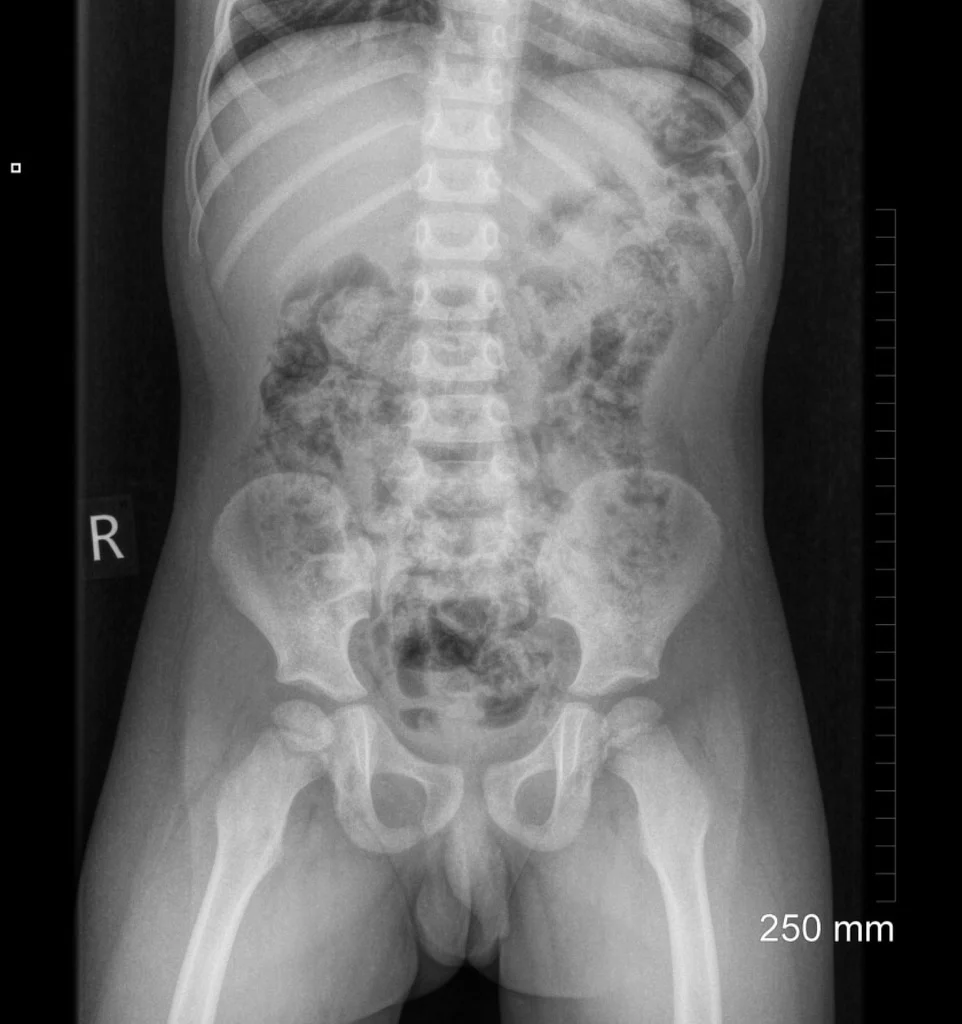

The supine chest view of the neonatal patient is a common radiographic examination when examining preterm patients 1.although not overall technically demanding, the radiographer should allocate time to ensure little to no repeats are required.

When the chest radiograph also includes the abdomen, look out for the umbilical clip. These are plastic clips used to clamp the umbilicus before it is cut at birth. Baby chest x ray technique : In young children, the patient lies on the table and the hands are held above the head. Chest radiographs •systematic review of chest radiographs is necessary for accurate evaluation.

Supply with lead apron and gloves, and have parent hold arms above the baby’s head with one hand and legs with other hand, to prevent rotation of the body. The federal food, drug, and. Kamis, 20 januari 2022 tambah komentar edit. Interestingly this improved and dropped to 8% in the second month, possibly as radiographers became more competent with the. Supply with lead apron and gloves, and have parent hold arms above the baby’s head with one hand and legs with other hand, to prevent rotation of the body.